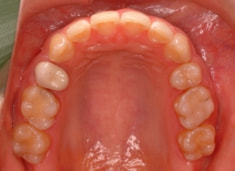

治療後(1年9ヶ月後)

治療開始から1年7ヶ月後